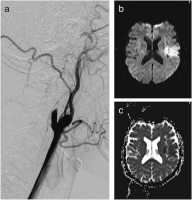

Abbildung 1: Diffusionsgewichtete MR- sowie repräsentative Angiographieaufnahme einer 37jährigen Patientin mit Dissektion der linken A. carotis interna (ACI) unter jahrelanger Therapie mit D-Penizillamin bei Morbus Wilson. Die Angiographie (a) zeigt einen spitz auslaufenden Verschluß des proximalen Gefäßabschnittes und die MRT (b, c) einen Mediaterritorialinfarkt mit entsprechender Diffusionsstörung (DWI, B1000[trace] [b] und ADC-Map [c]).